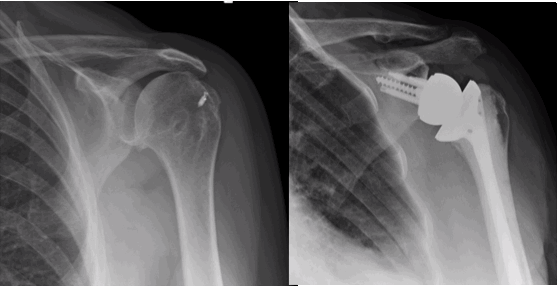

In a reverse shoulder replacement the orientation of the joint is changed such that an artificial ball is fixed to the shoulder blade and a socket is fixed to the humerus. A reverse shoulder replacement is used in patients where the rotator cuff is torn or deficient.